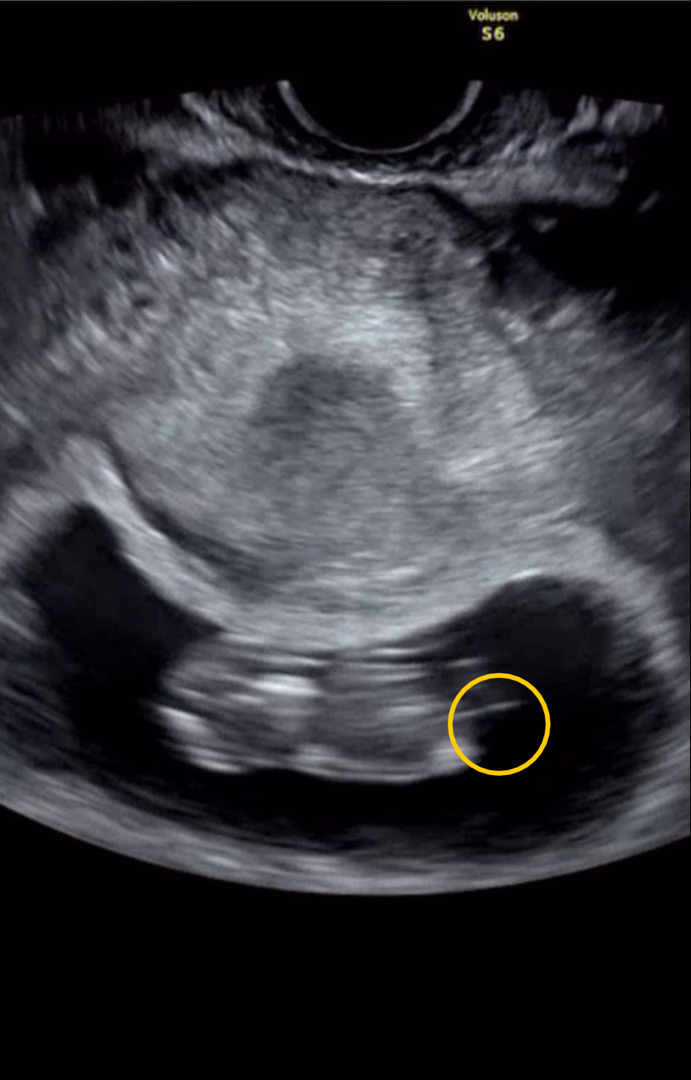

네 탯줄입니당

잠깐이지만 꼬물꼬물 다리를 움직이는걸 봤어요ㅎㅎ다리사이에 꼬리같은 줄이 흔들리던데 탯줄이죠??

살랑살랑 흔들리더라구요ㅋㅋ신기해요!!